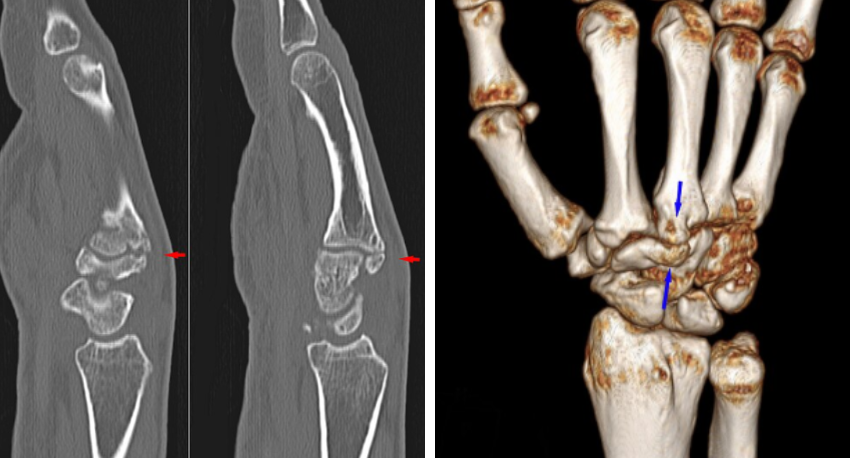

영상의학 검사: X-ray, CT, MRI로 단단한 뼈 돌출 확인 및 감별